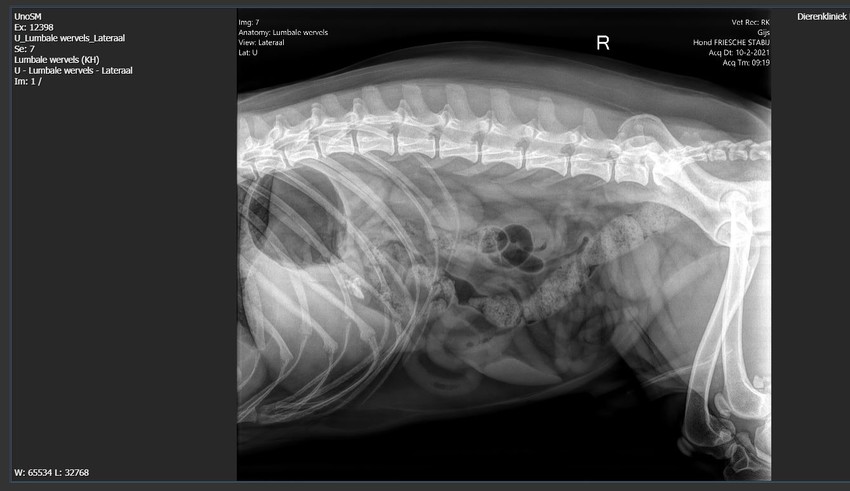

Aangezien ik natuurlijk wel nieuwsgierig was naar de foto's heb ik deze opgevraagd bij de dierenarts

Nou ik heb de rest van de foto's die eerder al gemaakt waren ook ontvangen

Aangezien links en rechts overal gelijk is zal ik ze niet allemaal plaatsen

Onderrug